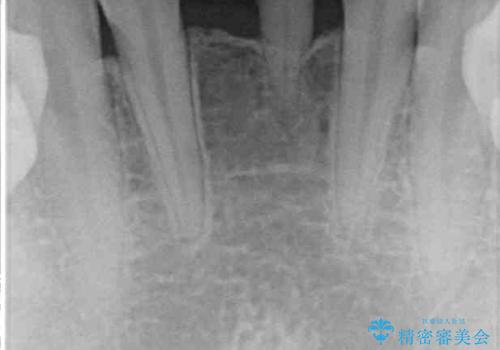

- 下顎前歯に乳歯が残っており、欠損もしていることを気にして来院された患者様です。

舌の突出癖が顕著にあり、上下前歯が非接触となっており、上顎前歯が前方に突出している状態でした。

ワイヤー装置により矯正治療を行うとともに舌突出癖改善のためのトレーニングをしっかりと行っていただき、咬み合わせが安定した位置となったタイミングで下顎前歯にブリッジの仮歯を装着していく計画としました。